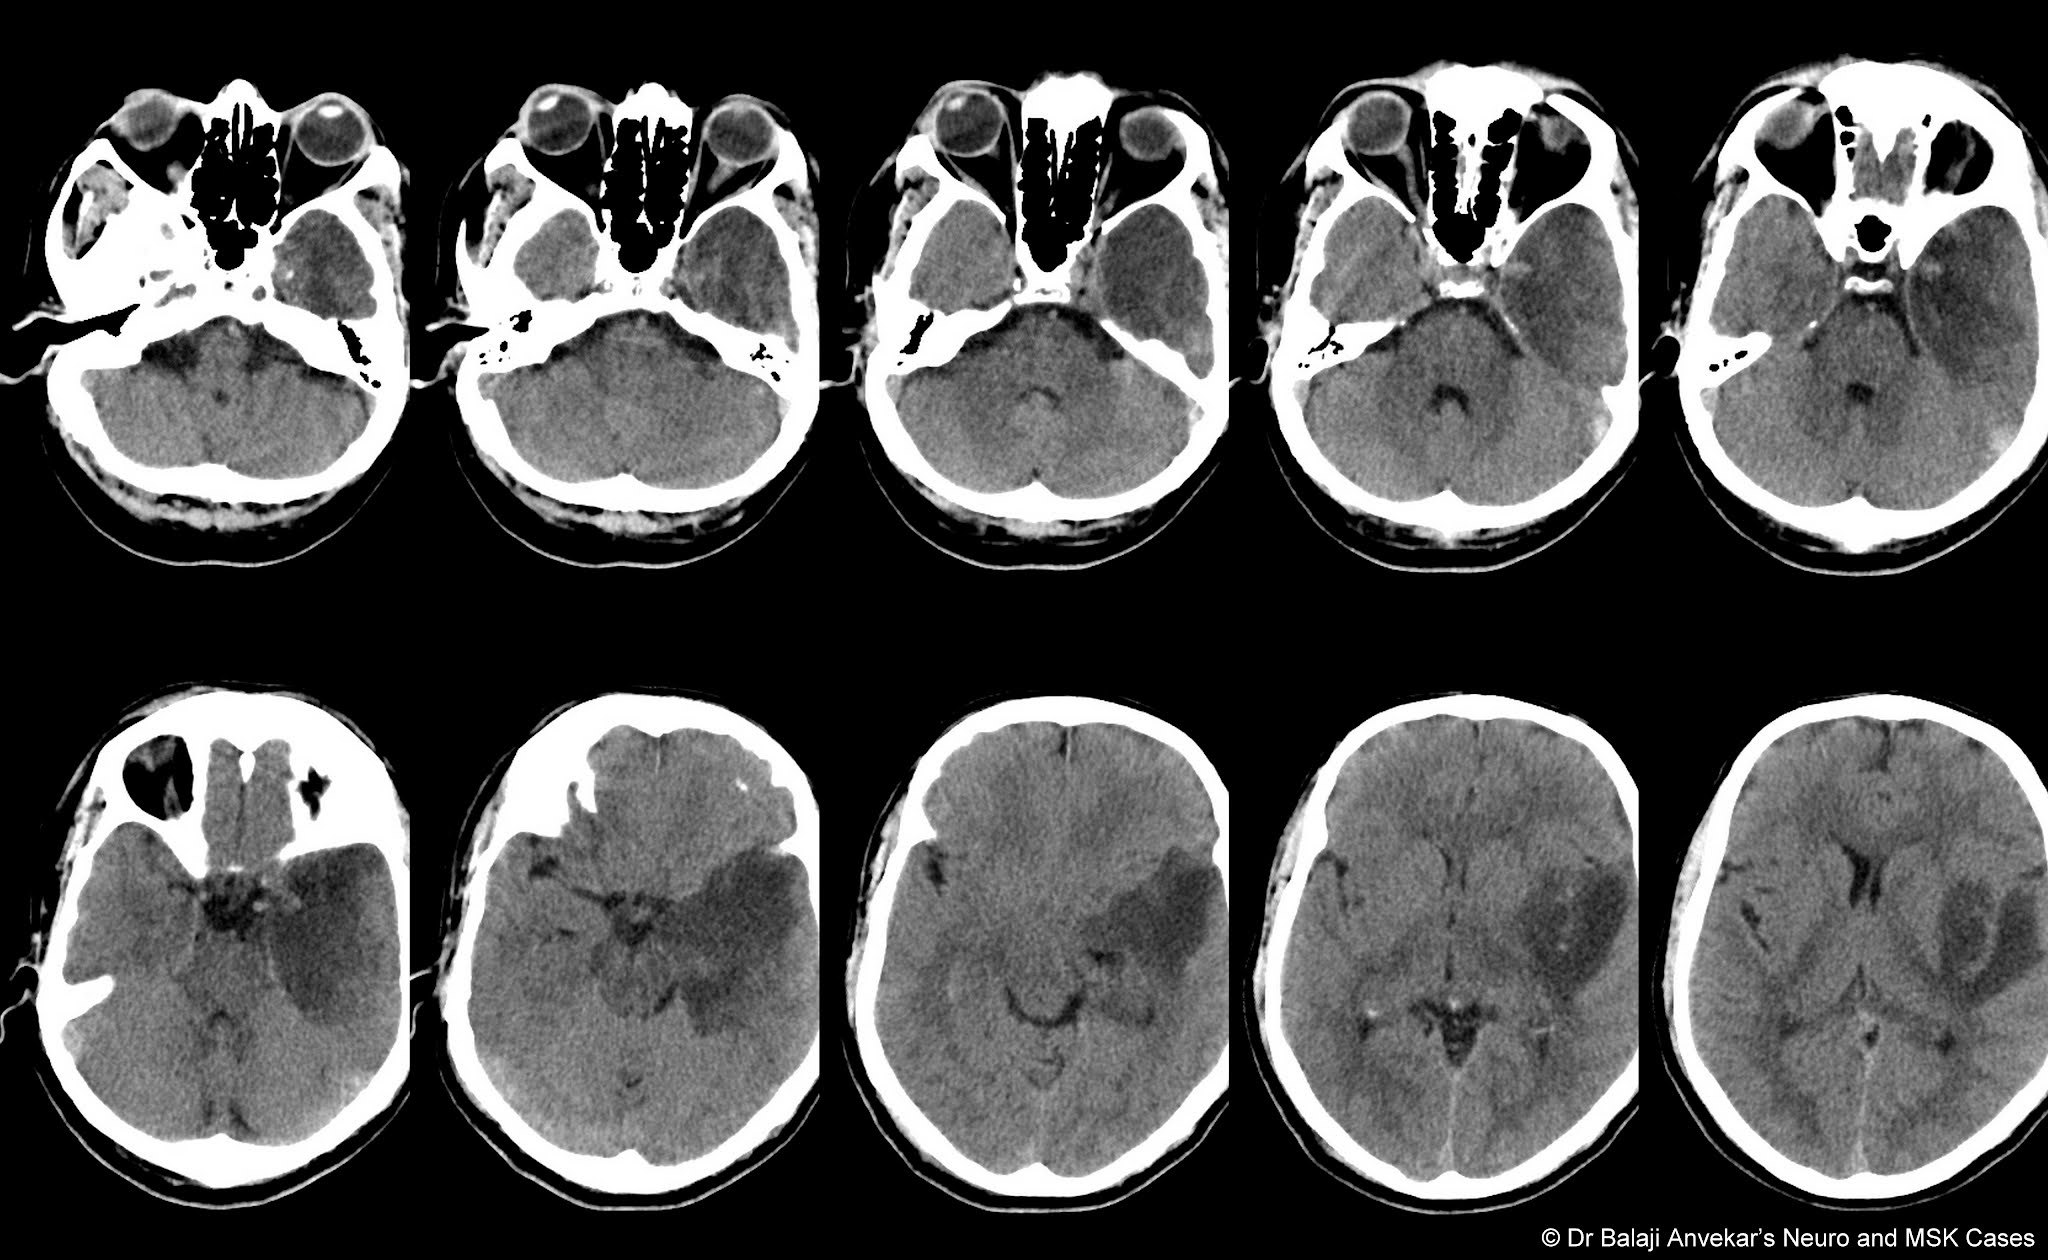

Isolated Superficial Sylvian Vein Thrombosis MRI

- Isolated Superficial Sylvian Vein Thrombosis MRI